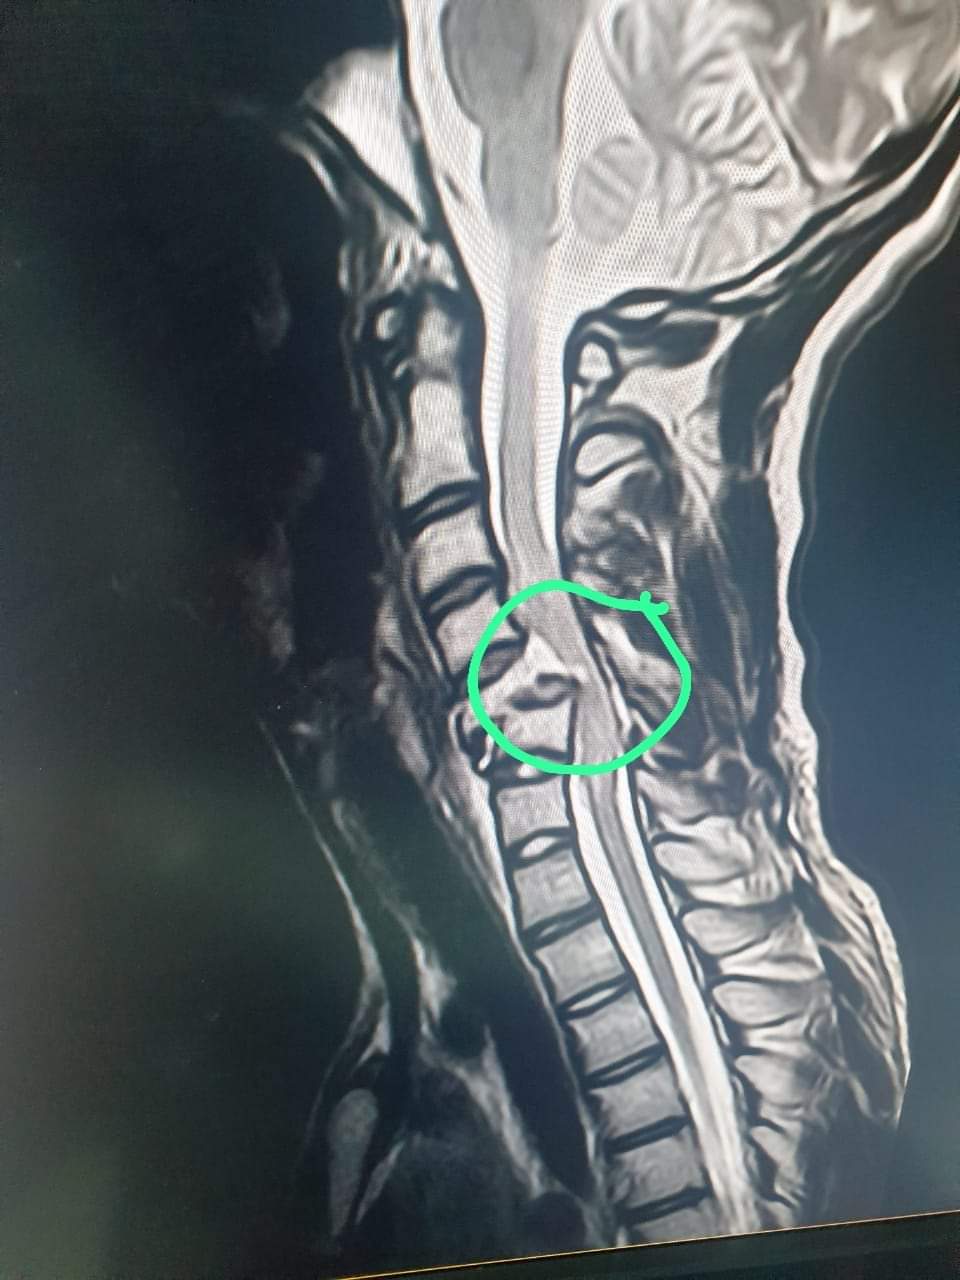

وأشار الدكتور بيشوي نبيل، في منشور له عبر صفحته علي فيس بوك، إلي أن سبب الإصابة أن الطالب كان بيلعب مع أصحابه "تريند" جديد على التيك توك، متابعا: الولد جاله كسر في الفقرات العنقية وضغط شديد على النخاع الشوكي، وبنسبة كبيرة مش هايتحسن، قائلا: ولد 13 سنة اتشل بسبب لعبة !!! بسبب هزار سخيف متخيلين إحنا وصلنا لإيه؟

وظهر في الفيديو مجموعة من طلاب المدارس وهم يصطفون بعضهم البعض ويركض زميلهم ويدفعونه إلى الأعلى ثم تركوه فسقط أرضا ونتج عنه إصابته بكسر في فقرات الرقبة واشتباه في شلل.